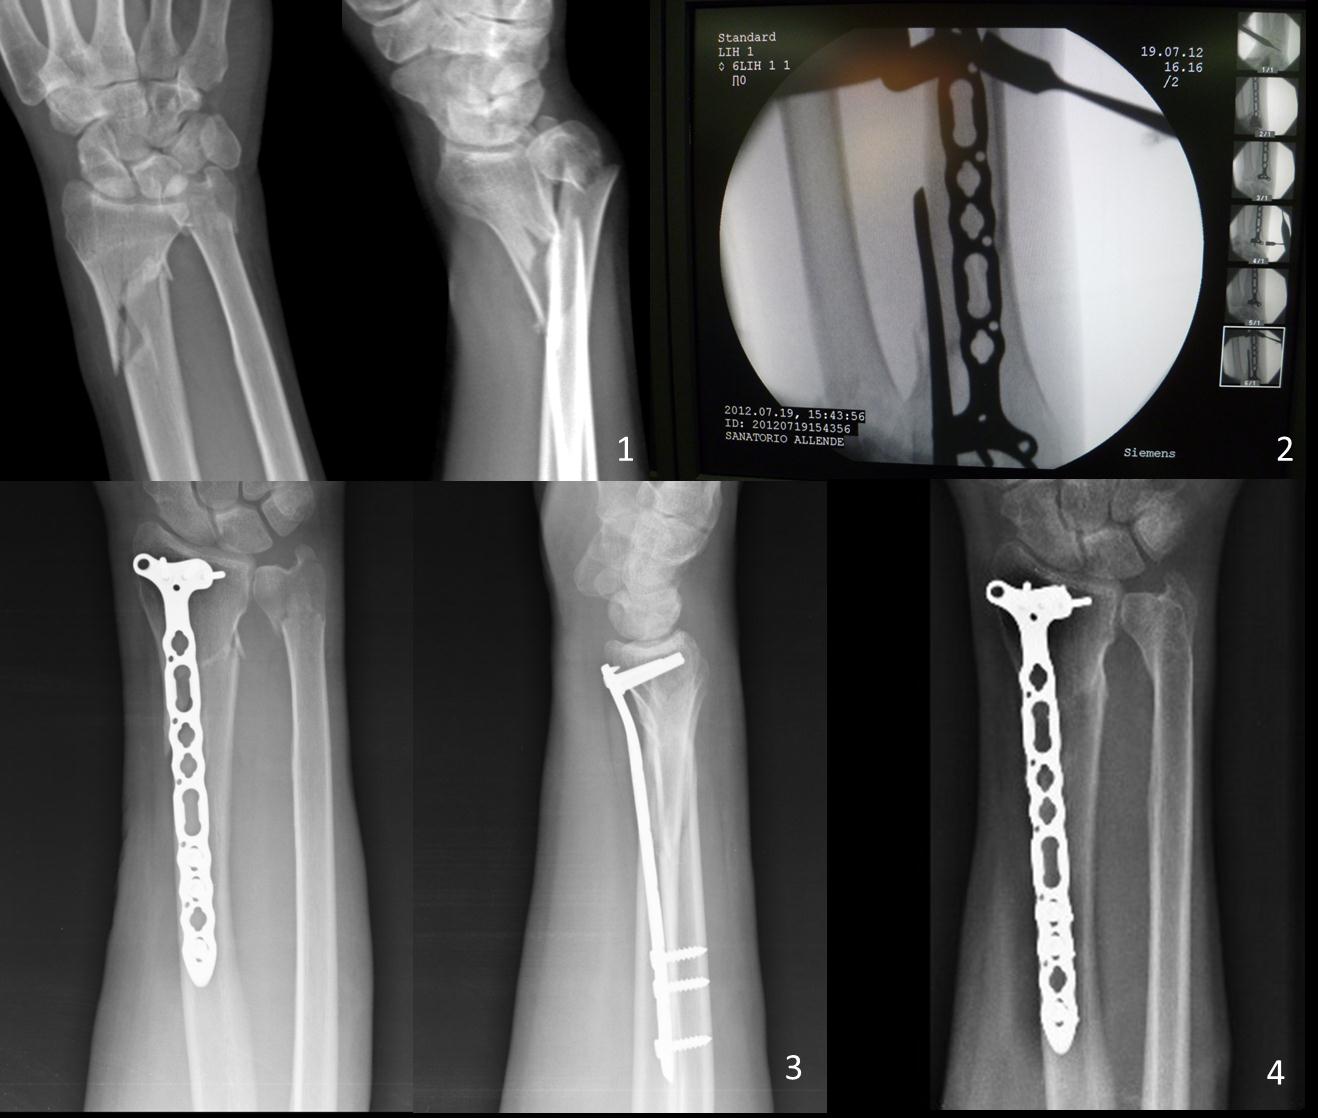

Osteosíntesis percutánea con placas volares bloqueadas en fracturas metafisarias distales de radio Descripción de la técnica y resultados preliminares. [Percutaneous volar locked plate fixation in metaphyseal fractures of distal radius: technical description and preliminary results].